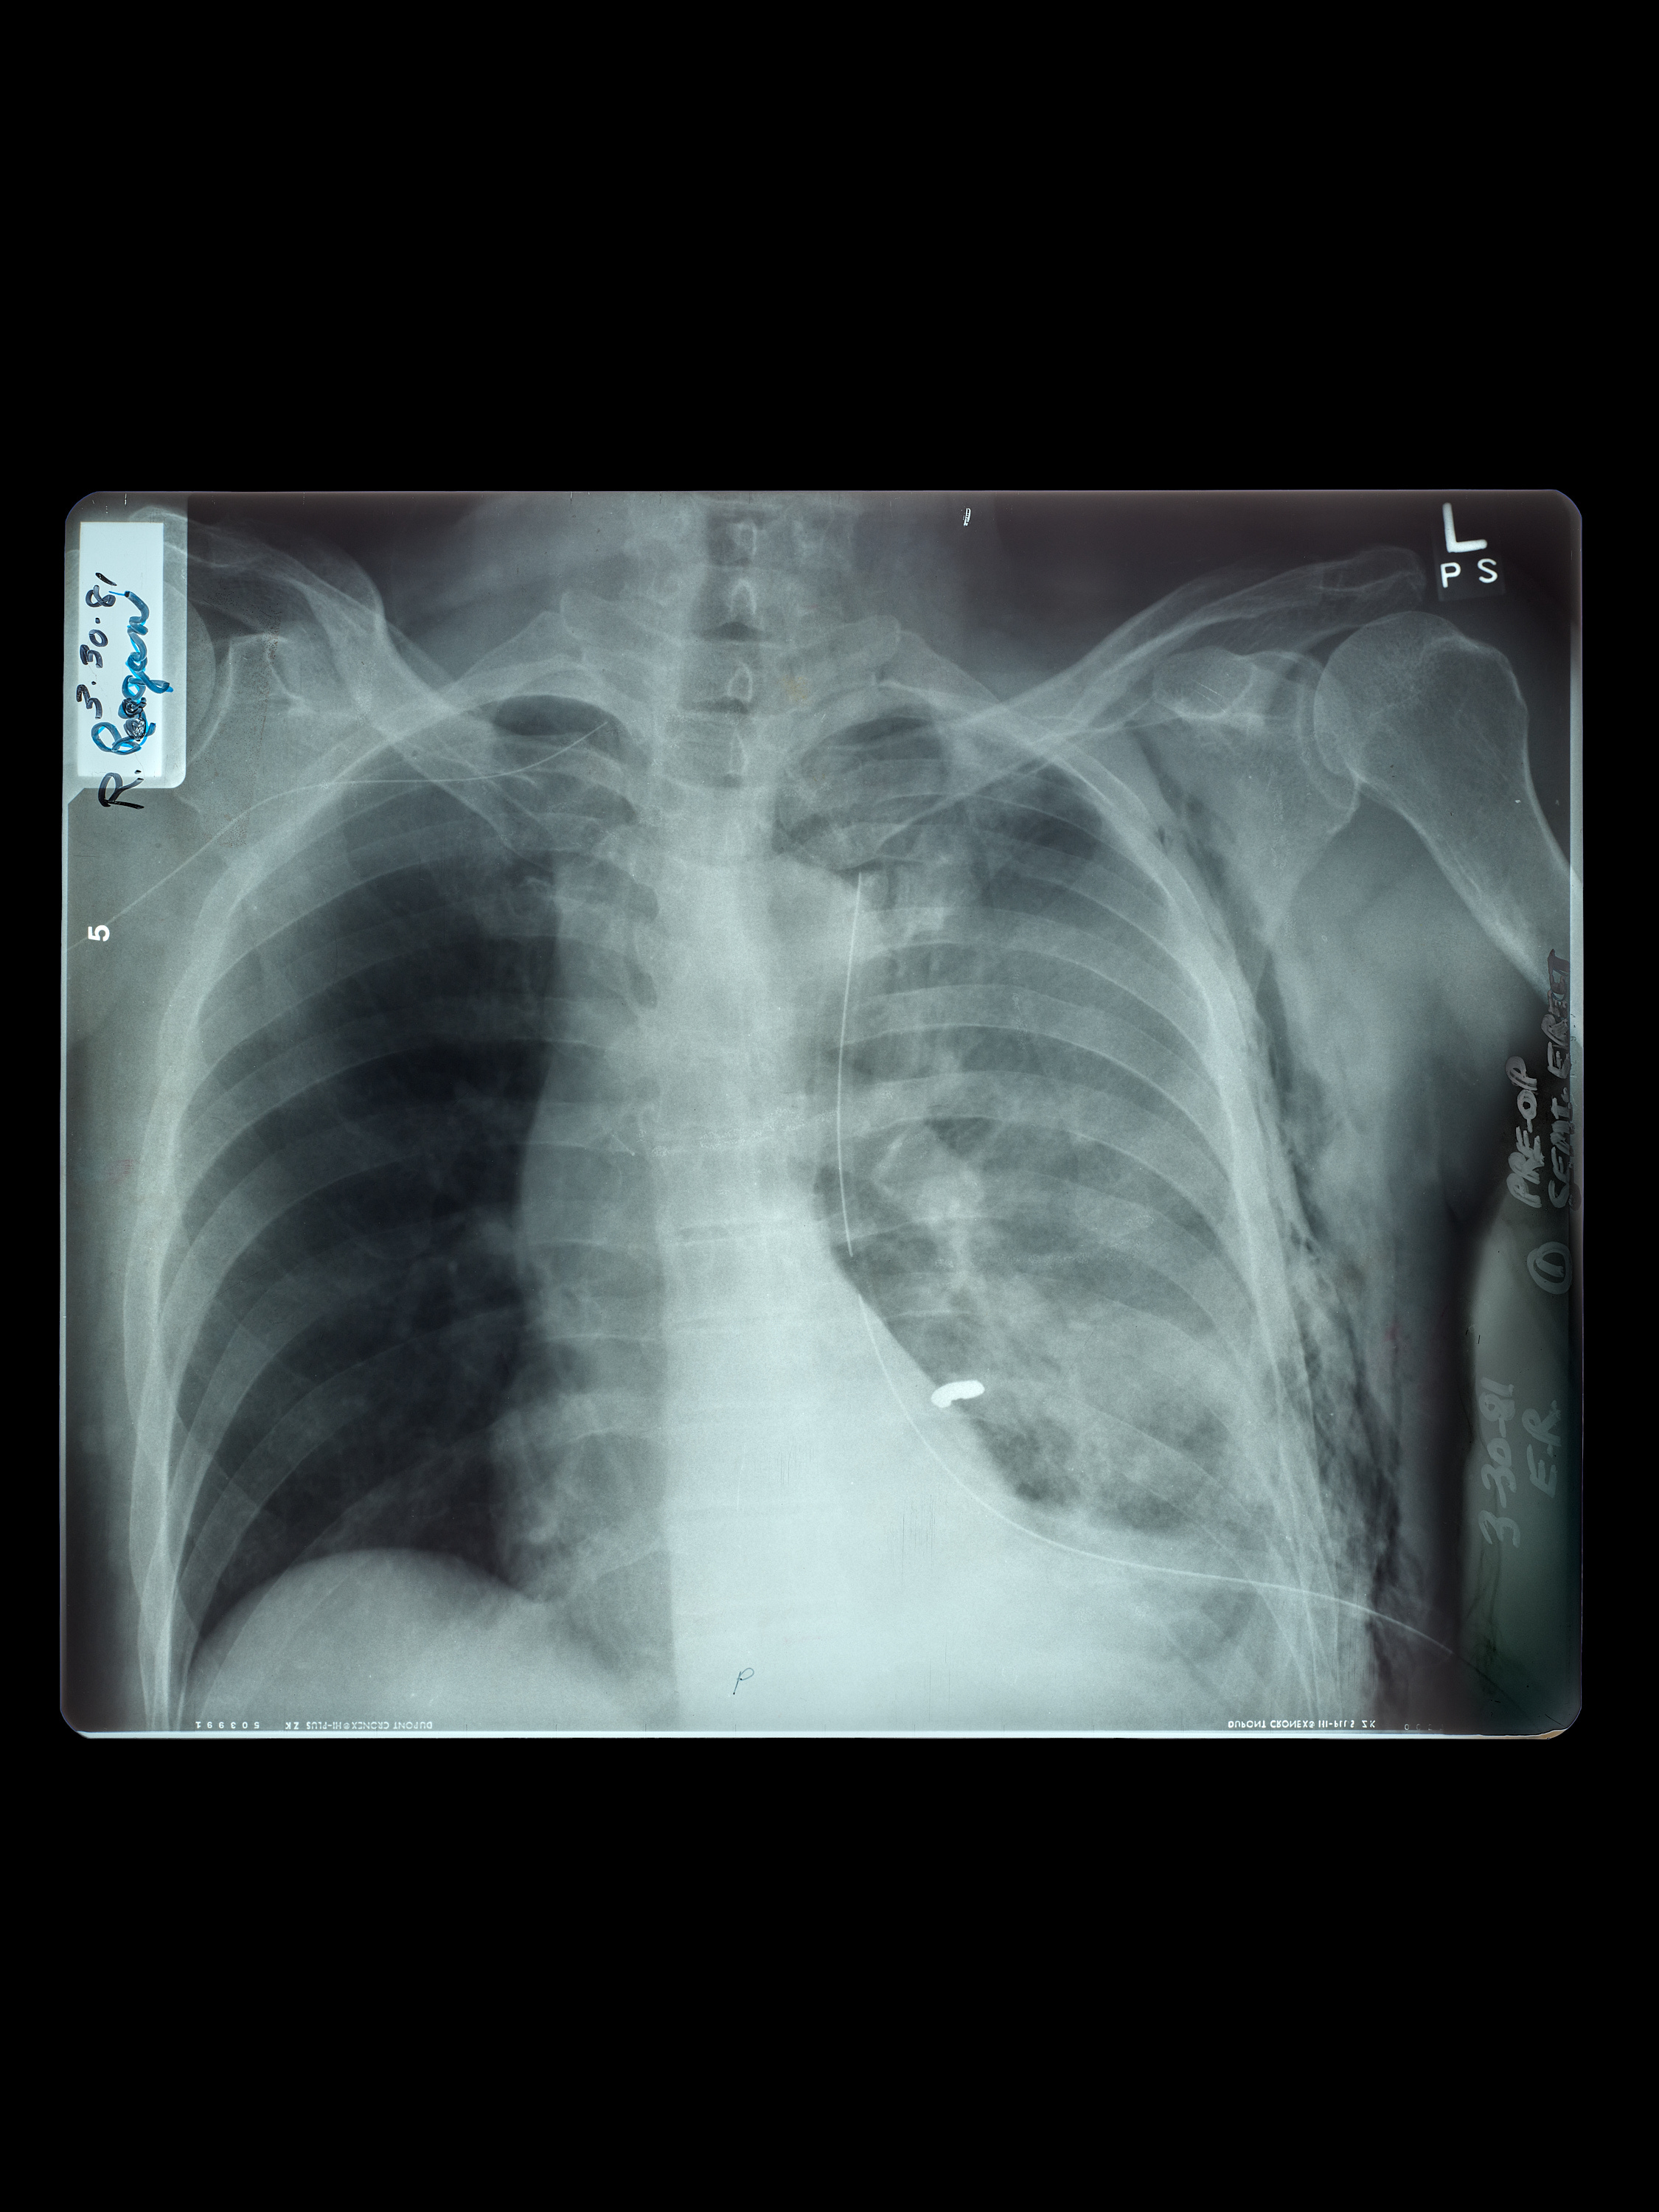

At first, no one realized the President had been shot. It wasn’t until Parr noticed bright, frothy blood on Reagan’s lips—a classic sign of a lung injury—that they headed directly for the hospital. While Reagan and Parr were initially unaware, the bullet from Hinckley’s sixth and final shot had ricocheted off the limousine and struck Reagan under his left arm, where it punctured his lung and stopped less than an inch from his heart. As he was rushed into the operating room, the President attempted to defuse the gravity of the situation with humor, saying to the doctors, “Please tell me you’re all Republicans.”